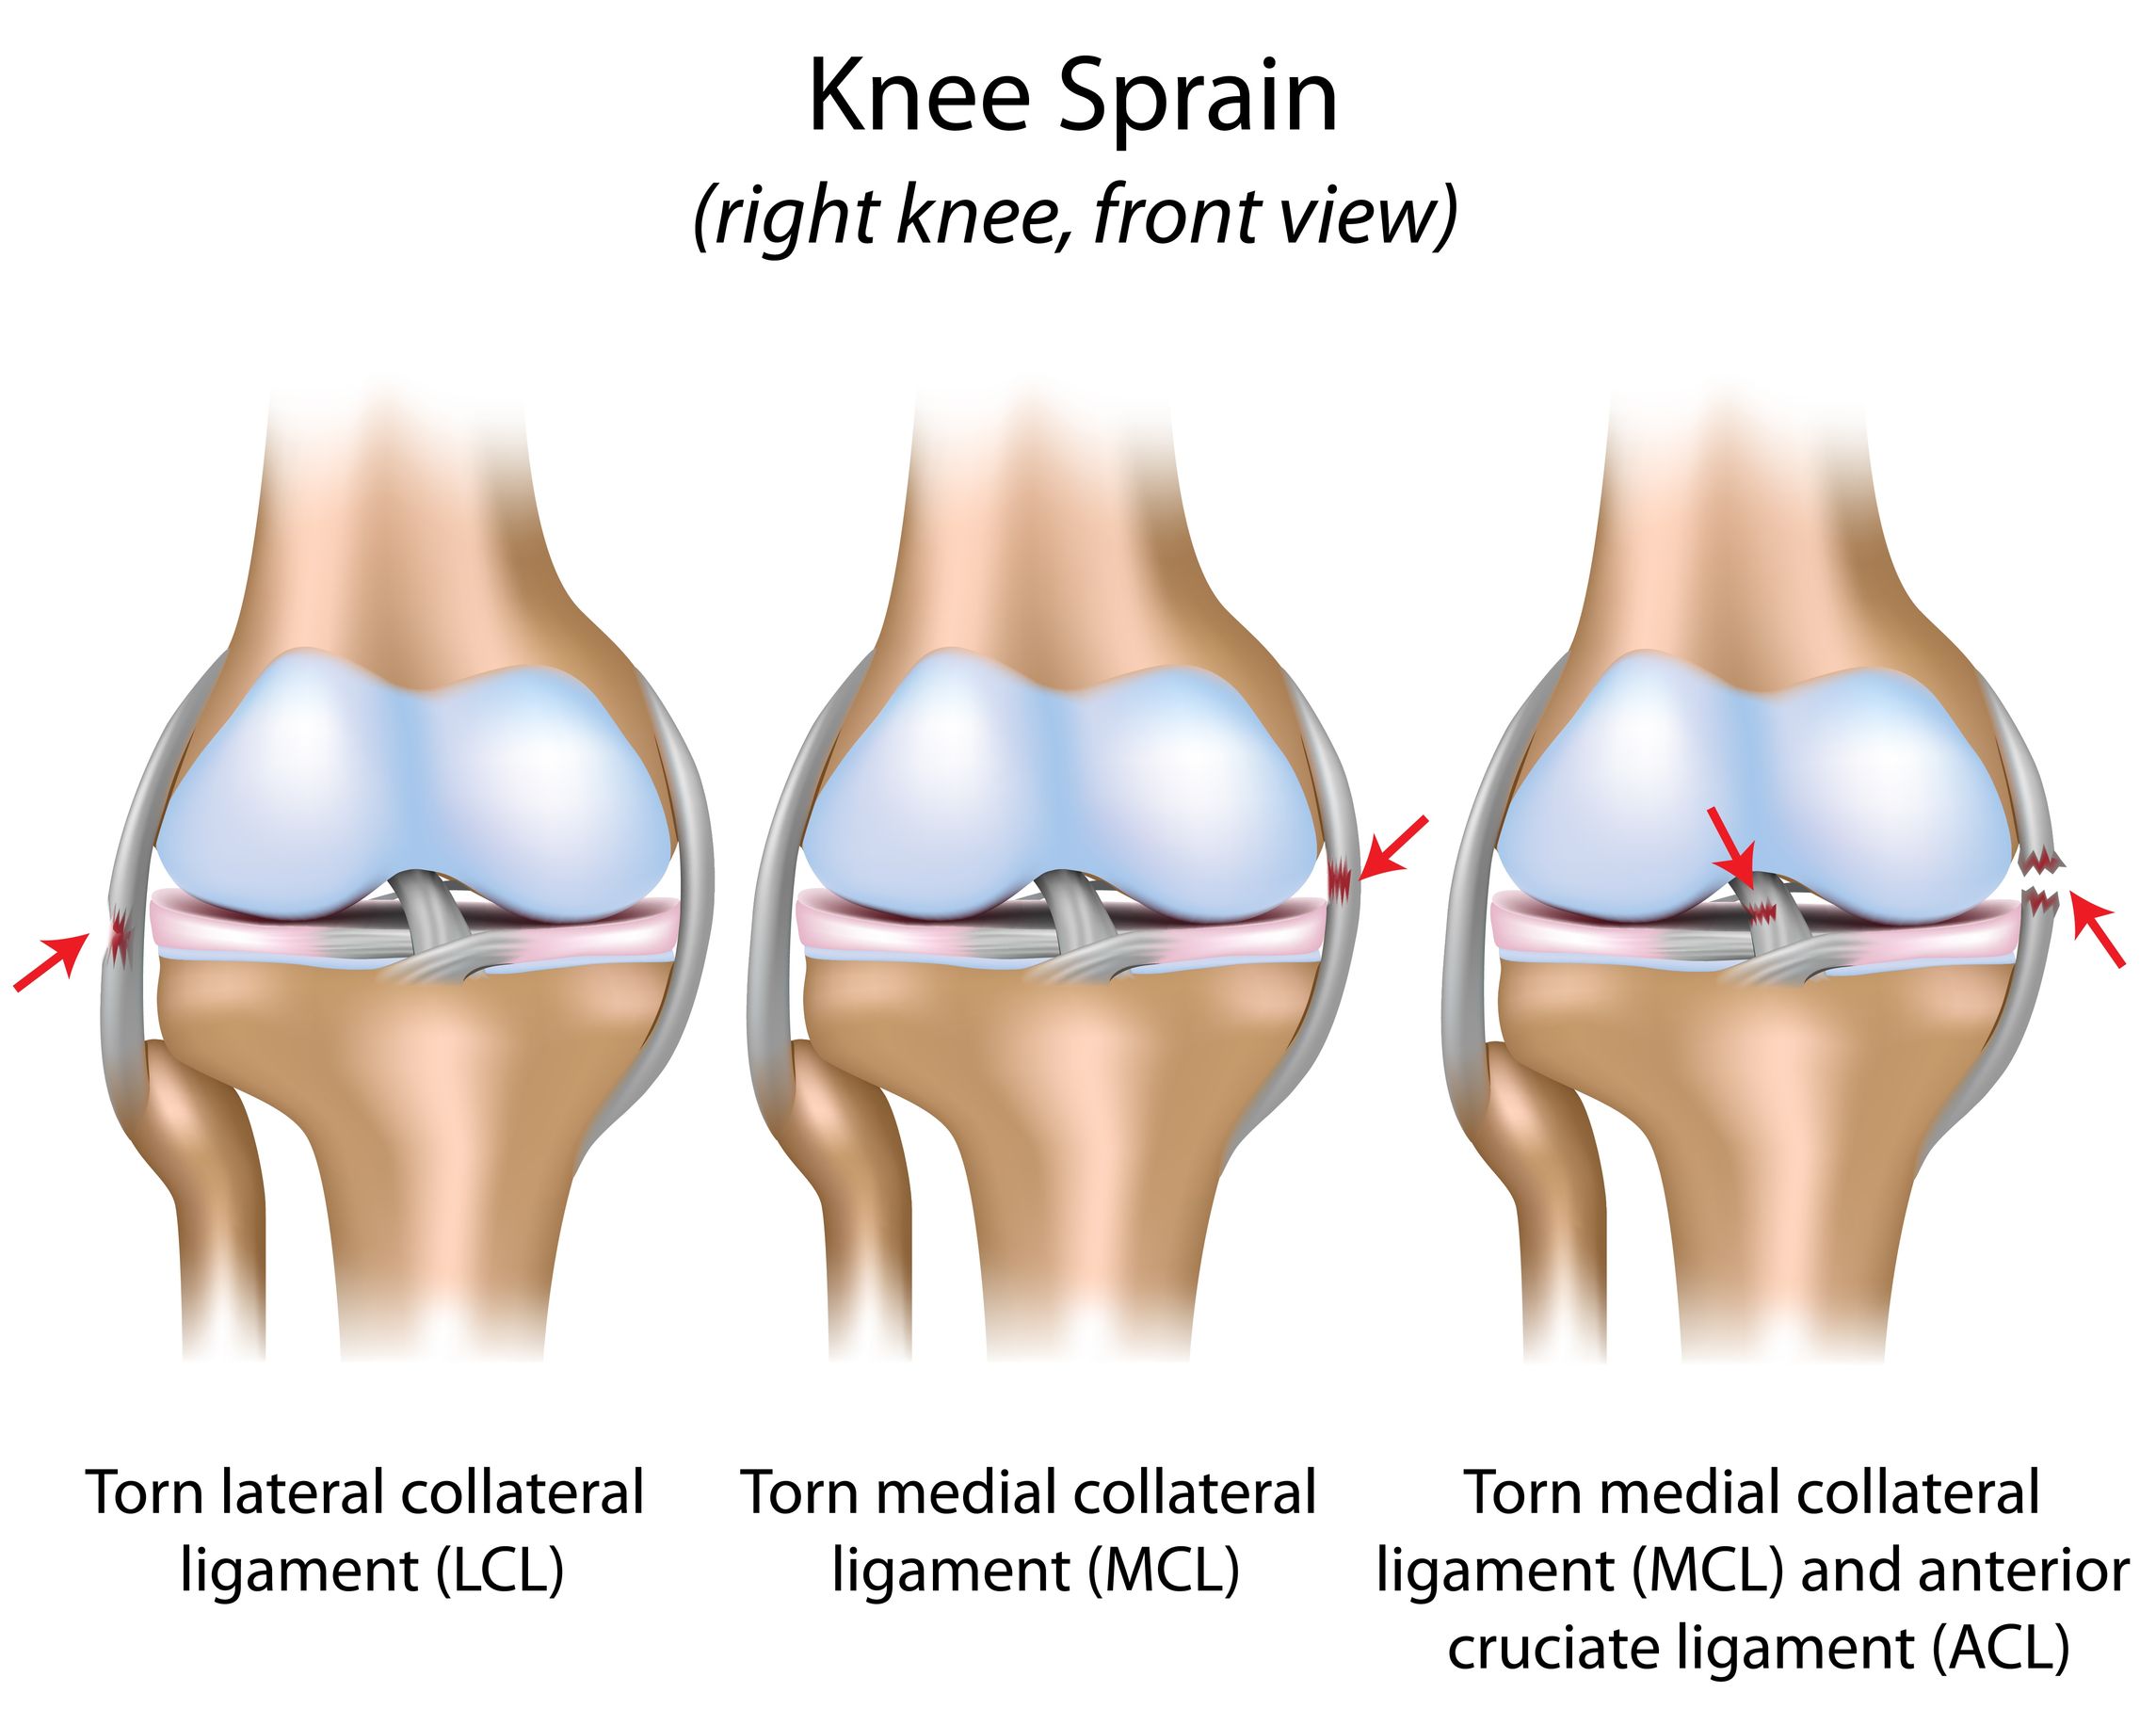

Строение коленного сустава. Повреждения мениска. Разрыв крестообразной связки. Гончаров Е.Н.